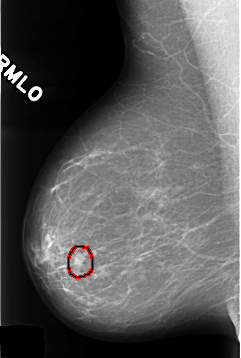

C_0319_1.RIGHT_MLO

FILE: C_0319_1.RIGHT_MLO.OVERLAY

TOTAL_ABNORMALITIES 1

ABNORMALITY 1

LESION_TYPE MASS SHAPE LOBULATED MARGINS CIRCUMSCRIBED

ASSESSMENT 3

SUBTLETY 5

PATHOLOGY BENIGN

TOTAL_OUTLINES 1

BOUNDARY